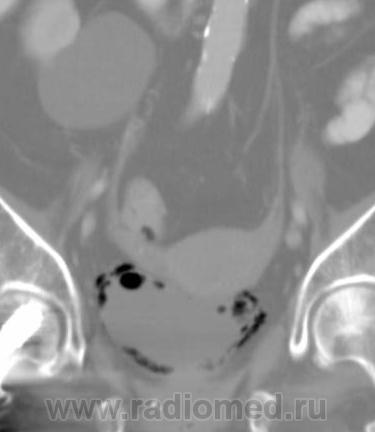

О чём могут говорить такие "газовые структуры" в области мочевого пузыря?

Наличие газа в мочевом пузыре может говорить о многом. Например стоял катетр Фолея, состояние после цистоскопии, эмфизематозный цистит, наличие фистулы.

А, чем именно, будет характеризоваться эмфизематозный цистит? При нем "пузырьки газа" локализуются в слизистой оболочке или где?

В просвете, может быть и в самой стенке. Смотрите здесь:

процесс в стенке в данном случае.

У женщины киста правой почки, подозрение на жировой гепатоз, стержень в головке и шейке правого бедра (остеосинтез). А про воздух возле/в стенке мочевого пузыря... не было ли оперативного вмешательства в малом тазу? И без аксиальных срезов явно я бы не сказала, где конкретно воздухblush...

Фик с ней с кистой... И какая разница аксиалы и короналы... Да, толстоваты срезы, эффект усреднения. Но я бы думал в сторону язвенного/гангренозного цистита (эмфизематозного цистита). Естественно, анамнез и клиника и всё встанет на свои места. На состояние после катерера не очень похоже...